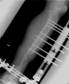

Initiialy had AO ext fixator followed by muscle flap done. Subsquently had bone transport done in tandem with Orthofix fixator

Progress of bifocal bone transport in tandem